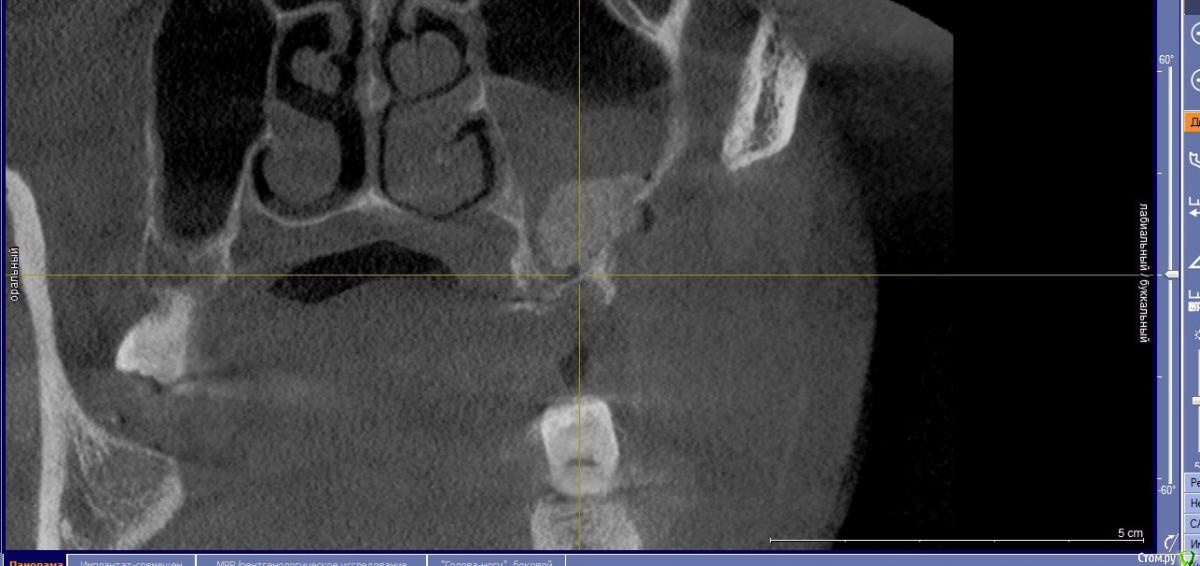

Bier Опубликовано 27 августа, 2016 Поделиться Опубликовано 27 августа, 2016 В пазухе отек, а вот кость придется добавлятьА что за инородное тело на 3м снимке? Ссылка на комментарий

Доктор Добрых Дел Опубликовано 27 августа, 2016 Поделиться Опубликовано 27 августа, 2016 Это не жидкость. Отек слизистой. Думаю материал в кость вряд ли превратится так как с костью практически не контактирует, так что лучше сразу убрать и переделать. Ссылка на комментарий

колесников Опубликовано 27 августа, 2016 Поделиться Опубликовано 27 августа, 2016 Дайте мне надежду в которую я буду верить))Ну отёк может и сойдёт,только синуслифтинг не удался. Отслоили недостаточно,весь графт на щёчной стенке остался. Ждать смысла нет. 4 Ссылка на комментарий